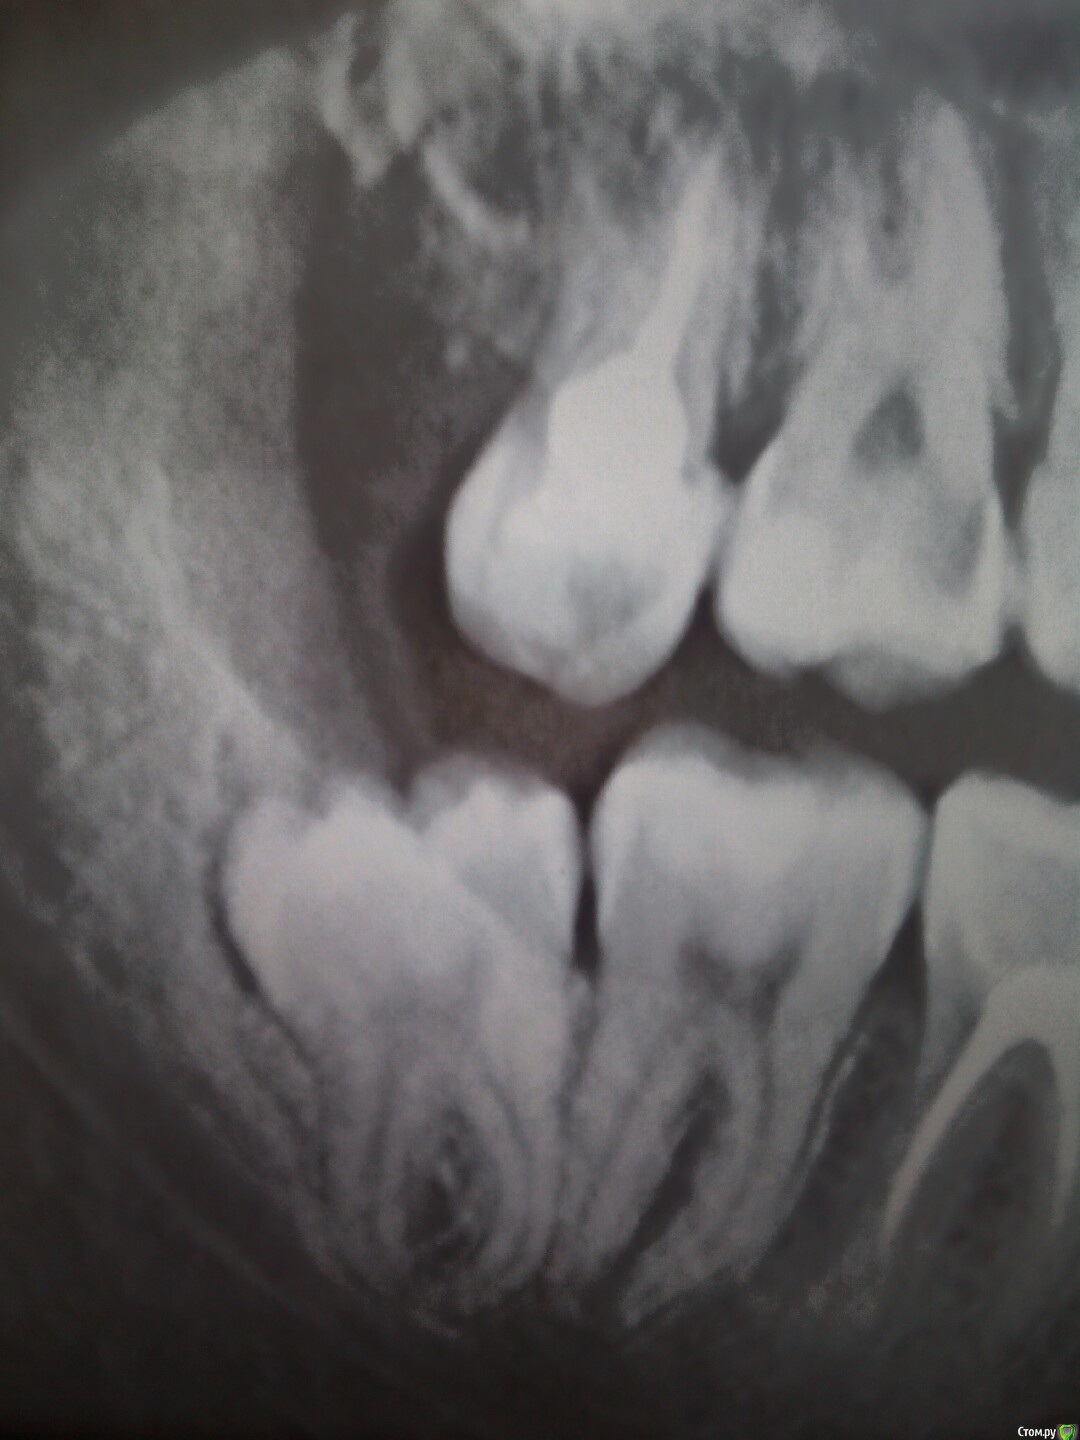

Рыжъ Опубликовано 12 мая, 2015 Поделиться Опубликовано 12 мая, 2015 (изменено) Здравствуйте, уважаемые доктора! Ж, 28 лет. Нижняя правая восьмерка не прорезалась до конца, из-под десны кокетливо выглядывает один ее кончик. Проблем не доставляла никогда, не болела, другая нижняя восьмерка в зубном ряду ровненько стоит. Три дня назад появились спонтанно боли на термические раздражители, на горячее и холодное. Болит после раздражителя примерно час еще. Боль сильная, ноющая. Не пульсирует. Десна розовая, не увеличена, нигде нет припухлостей. Но боли адские. Ночью болит сама по себе. Я очень мучаюсь. Сделала рентген, снимки прилагаю. Подскажите, какова моя тактика? Удалять восьмерку или нет? Можно ли сохранить зуб в таком вот состоянии? Не опасно ли это для семерки? Почему пульпитные боли начались, неужели из-за нехватки места для восьмерки? Изменено 12 мая, 2015 пользователем Рыжъ Ссылка на комментарий

Bier Опубликовано 12 мая, 2015 Поделиться Опубликовано 12 мая, 2015 пульпитные боли потому что где-то пульпит. Проверьте верхний 7й.Верхний 8й - удаляйте. Ссылка на комментарий

annda Опубликовано 12 мая, 2015 Поделиться Опубликовано 12 мая, 2015 А на верхнем 7м что за дефект чернеется вплотную к 6ке?Тут снимок в прикусе будет самым точным,но и прицельный можете показать. Ссылка на комментарий

red_butler Опубликовано 13 мая, 2015 Поделиться Опубликовано 13 мая, 2015 нужно искать пульпит, внимательно посмотреть 1.7 1.4 4.3 и 4.7 1 Ссылка на комментарий

Bier Опубликовано 14 мая, 2015 Поделиться Опубликовано 14 мая, 2015 по вашему снимку очень смущает верхняя 7ка (17й) Ссылка на комментарий